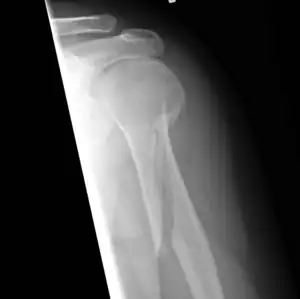

| An x-ray image of a spiral fracture to the left humerus of a 27-year-old male. The injury was sustained during a fall. | |

Spiral fracture is a fracture that may occur when a rotating force is applied along the axis of a bone.[1]